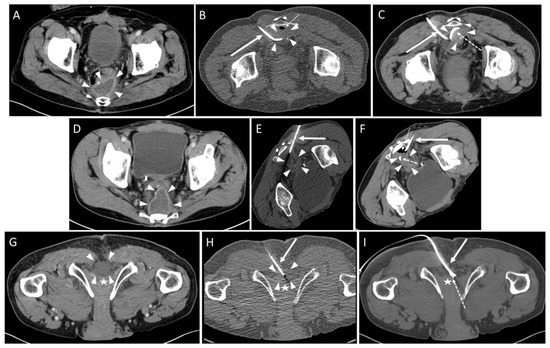

| Approach | |

| parasacral | 29 (72.5%) 3 |

| paracoccygeal | 10 (25.0%) 3 |

| infracoccygeal | 1 (2.5%) 3 |

| Access path | Count |

| transpiriform | 8 (20.0%) 3 |

| infrapiriform | 31 (77.5%) 3 |

| transperineal | 1 (2.5%) 3 |